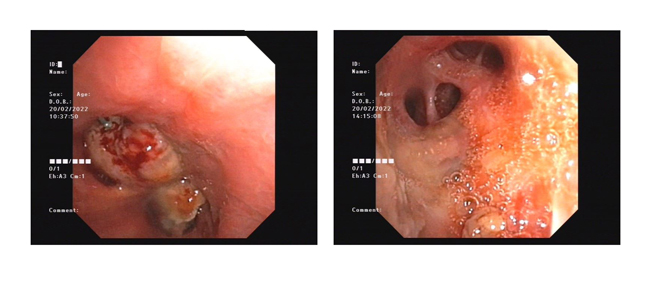

支氣管鏡下微波消融術(shù)前后對比

據(jù)黃德良主任介紹,劉健患者這次因肺鱗癌引起氣喘問題過來求治的。入院后經(jīng)過完善檢查診斷為右肺鱗癌并胸膜、肺門、縱膈淋巴結(jié)轉(zhuǎn)移,已是T4N2M1屬于肺癌IV期了。“當時情況非常緊迫,患者右主支氣管主干完全堵塞,左主支氣管堵塞,雖然之前在外院做了支架,但支架近端也有腫瘤導致大部分的堵塞。病人呼吸困難,經(jīng)皮血氧低于80%。在麻醉科,氣管鏡室和8樓醫(yī)護共同努力下給病人行右主支氣管腫物微波消融術(shù),術(shù)后氣道恢復通暢,右肺完全復張!患者手術(shù)中還出行反復出血,情況非常不理想,幸得患者家屬無條件的信任,經(jīng)過團隊的共同努力,歷時3個多小時的手術(shù)還是順利完成。目前病人已經(jīng)可以下床走路,經(jīng)皮血氧恢復至95%?!?月15日,經(jīng)過黃教授團隊的評估后,患者接受了介入化療方案,術(shù)后患者呼吸困難癥狀得到進一步改善,指尖血氧好轉(zhuǎn)。在2月20日再次接受氣管鏡下雙側(cè)主支氣管腫物微波消融術(shù)。3月1日復查了CT,患者腫塊縮小,右肺復張。